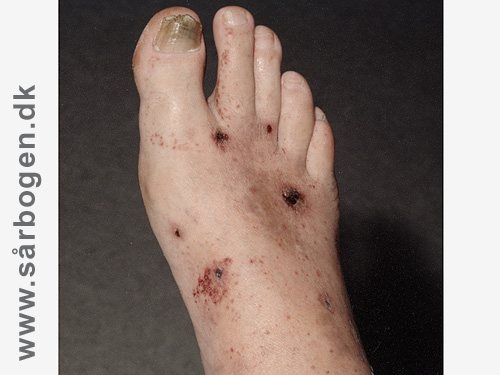

Buerger

Buerger-1

Buerger-2